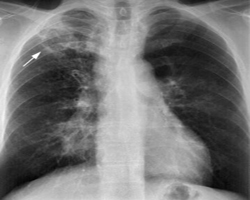

Chest and Tuberculosis (TB)

TB is caused by the bacterium Mycobacterium tuberculosis (M tuberculosis). TB is contagious. This means the bacteria is easily spread from an infected person to someone else. You can get TB by breathing in air droplets from a cough or sneeze of an infected person. The resulting lung infection is called primary TB.

TB can affect any organ system, although manifestations are most commonly related to the chest. The lungs are the most common and often the initial site of involvement. Chest involvement is most commonly pulmonary, followed by lymph nodal and pleural disease (latter two are included under EPTB). Chest wall, cardiac, breast, and skeletal involvement can also occur in the thorax.

Tuberculosis (TB) is a disease caused by bacteria that are spread through the air from person to person. If not treated properly, TB disease can be fatal. People infected with TB bacteria who are not sick may still need treatment to prevent TB disease from developing in the future. Learn to recognize the symptoms of TB disease and find out if you are at risk.

The primary stage of TB does not cause symptoms. When symptoms of pulmonary TB occur, they can include: